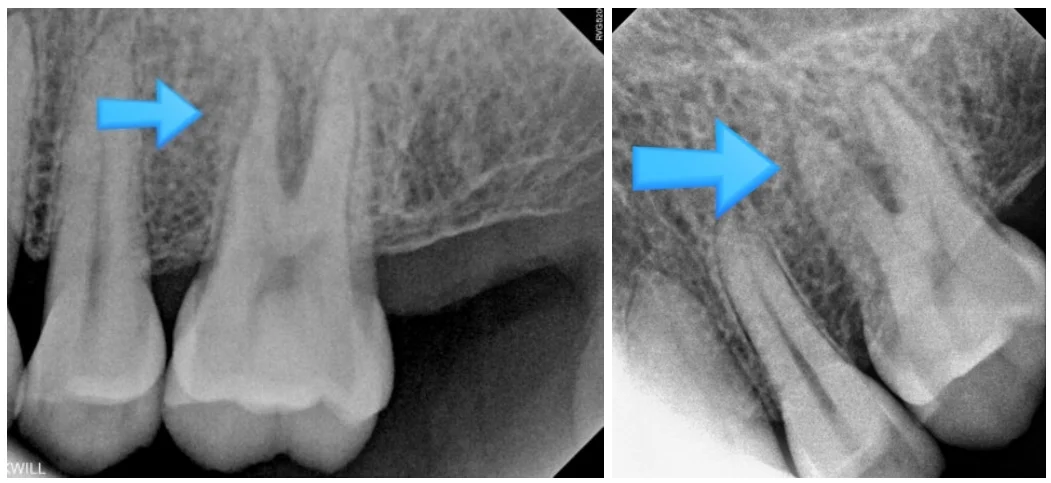

화살표로 표시된 치아 주변 잇몸이 씹을 때 불편함이 느껴지고, 자주 붓는 증상이 있다고 말씀하셨습니다.

보다 정확하게 확인하기 위해 해당 부위를 확대하여 엑스레이 촬영을 진행해 보았습니다.

화살표로 표시된 치아 뿌리 부위에서 다른 양상이 관찰되었습니다.

환자분은 건장한 체격의 남성으로 오랜 기간 큰 문제 없이 치아를 사용해 오셨다고 했습니다. 하지만 엑스레이에서 뼈가 일부 소실된 모습이 확인되었고, 이러한 소견을 바탕으로 치아 파절 가능성을 의심하게 되었습니다.

이러한 부분들을 종합적으로 검토한 결과 저는 치아 뿌리 파절 가능성이 높다고 판단하였고, 발치를 권해 드렸습니다.

설명을 충분히 들으신 뒤 환자분께서 발치에 동의하셨고, 실제로 발치 후 확인해 보니 치아 뿌리가 가로 방향으로 갈라져 있는 상태였습니다.